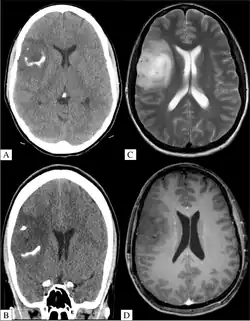

Oligoastrozytom, Grad 3 in der Schnittbildgebung. A, B: CT-Bilder mit aufgehellten Verkalkungen. C: MRT, T2-gewichtet, D: MRT, T1-gewichtet, mit Kontrastmittel, ohne Anreicherung im Tumor

Typischerweise erfolgt die Diagnostik durch eine Magnetresonanztomographie mit und ohne Kontrastmittelgabe oder durch eine Computertomografie (CT). Eine Kontrastmittelanreicherung zeigt nicht so sicher wie bei Astrozytomen einen Übergang zur Anaplasie an.

Die meisten Oligodendrogliome zeigen Verkalkungen, bei Grad 3 sind diese fast immer vorhanden.[5]